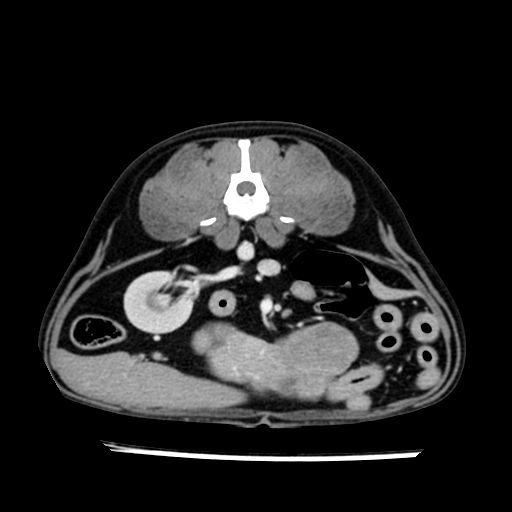

prescritto esame TAC

sequenza immagini limitata al fegato reni e surreni

le immagini ecografiche rispetto alla tac datano circa 7 mesi prima ,le surrenali sono normali nonostante il test acth sia risultato positivo .all’esame TAC dopo diversi mesi risultano aumentate armonicamente nel volume e si individua un forte sospetto di adenoma ipofisario .

sospetto adenoma ipofisario vs. meno probabilmente meningioma della base; intertiziopatia polmonare; lesione espansiva epatica, verosimilmente del lobo laterale sinistro, di sospetta natura neoplastica; lesioni spleniche di natura da definire; iperplasia/ipertrofia delle ghiandole surrenali, bilateralmente; vertebra di transizione del rachide toracico; tenosinovite cronica del muscolo bicipite brachiale di destra.

- Nessuna informazione diversa per quello che riguarda l’esame ecografico del fegato e la presa del contrasto si confermano le lesioni individuate e l’ipoenanchement in fase portale.

- la total body permette di escludere metastasi e di avvicinarsi all’interventistica